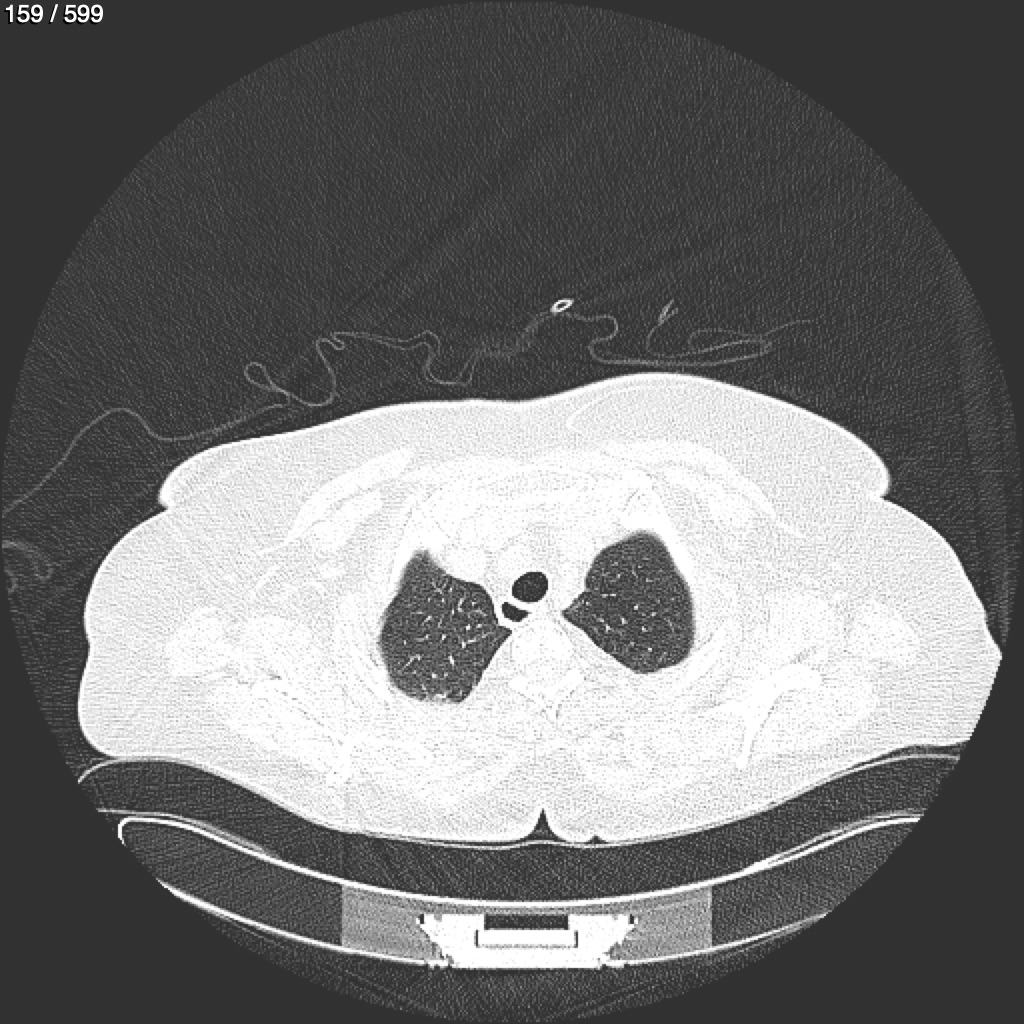

Home G​l​o​r​i​a​ ​G​l​a​d​y​s​ ​B​e​a​s​l​e​y​ ​-​ ​T​ó​r​a​x​ ​T​o​r​a​x​_​S​i​m​p​l​e​ ​(​A​d​u​l​t​o​)